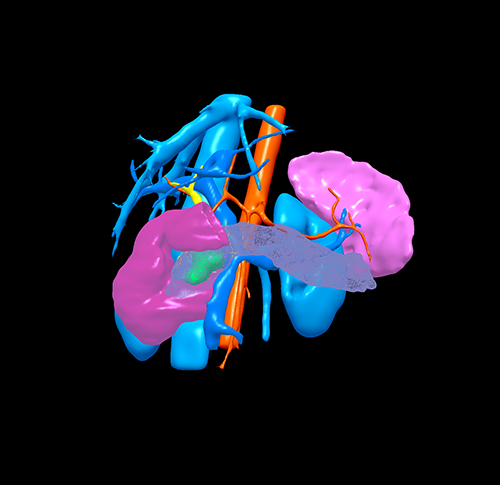

胰腺头颈假性乳头状瘤 -胰腺中段切除